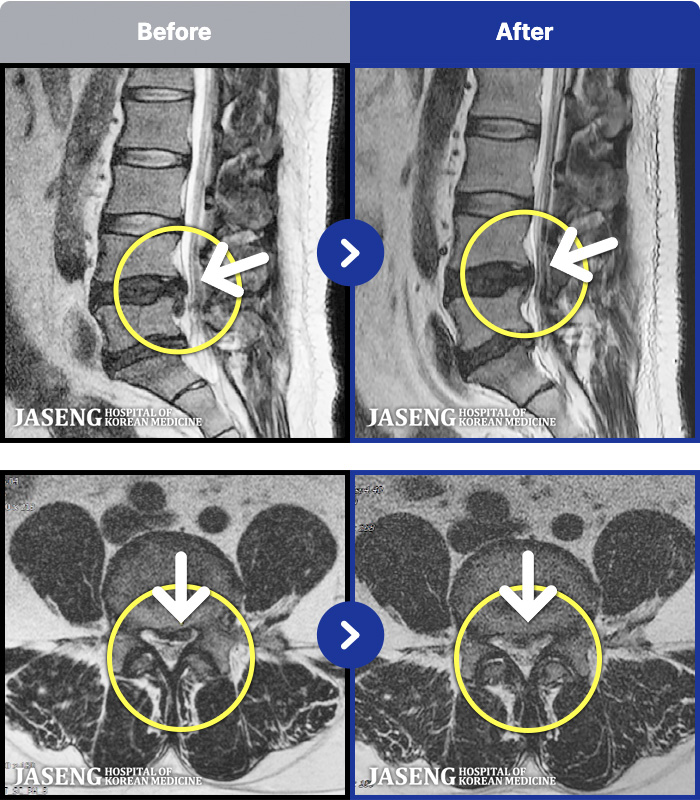

MRI ġ

1,301 MRI ũ ʸ Ȯϼ.